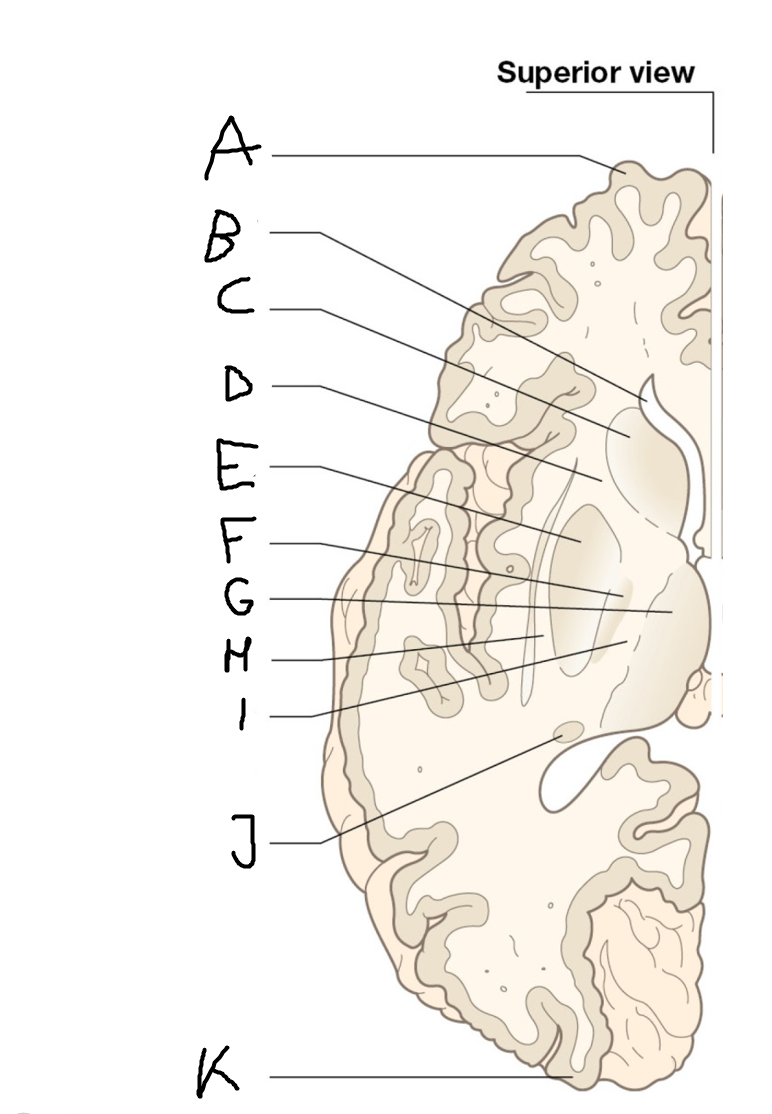

internal capsule (posterior limb)

B

anterior horn of lateral ventricle

C

head of caudate nucleus

D

internal capsule (anterior limb)

E

putamen

F

globus pallidus

G

Thalamus

H

External capsule

I

internal capsule (posterior limb)

J

tail of caudate nucleus